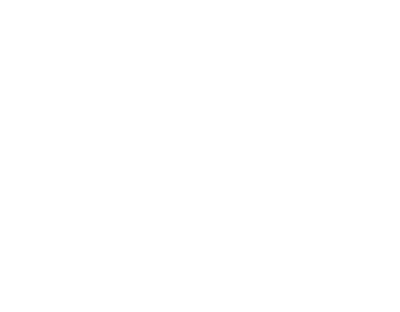

ヒトの歯もイヌ・ネコの歯も構造に大きな違いはありません。

エナメル質・象牙質・セメント質・歯髄となっています。